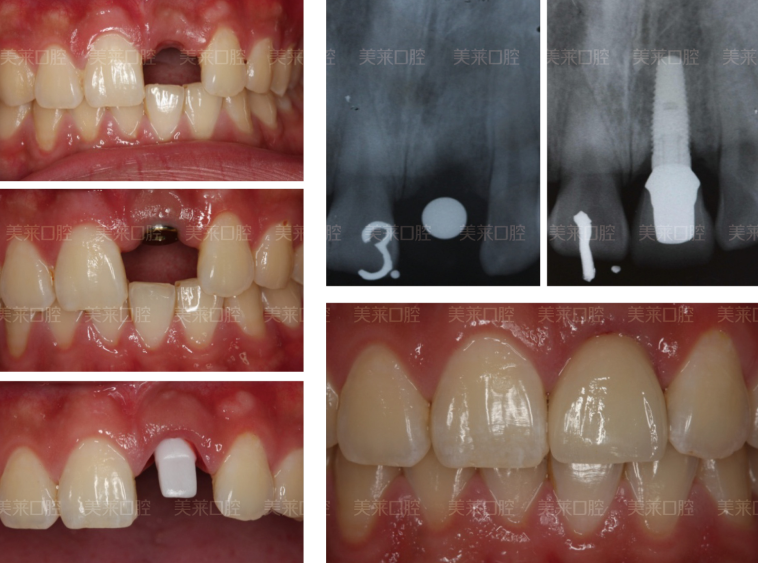

种植牙属于固定修复,对病人来说感觉舒适、无异物感,与传统的缺失牙固定修复相比,不需要借助邻牙,减少了其他天然牙的损伤。可以像真牙一样扎根在患者的口腔里,所以比传统镶牙更牢固,而且种植牙和天然牙的生物力学原理相同,天然牙把口腔内的咀嚼压力通过牙根传递到牙槽骨,种植牙把咀嚼压力通过人工牙根(种植体)传递至牙槽骨,所以种植牙能承受强大的力量,咀嚼效率比传统假牙有大幅度提高。所以种植牙不会影响其它牙齿的。

深圳美莱通过医学方式,将与人体骨质兼容性高的纯钛金属设计成精密的人工牙根,再植入缺牙区的牙槽骨内。经过1~3个月后,当人工牙根与牙槽骨密合后,再在人工牙根上制作牙冠。具有安全、舒适美观、坚固耐用优势,目前,种植牙已被口腔医学界公认为缺牙的修复方式。